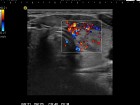

First examination (first row):

Clinical presentation: A 29-year-old woman was referred for evaluation of complaints suggesting hyperthyroidism. She had no eye signs.

Palpation: Both lobes were enlarged. No nodule was palpable.

Ultrasonography: Both lobes were enlarged, moderately hypoechogenic, inhomogeneous and displayed increased vascularization.

Diagnosis: Graves' hyperthyroidism.